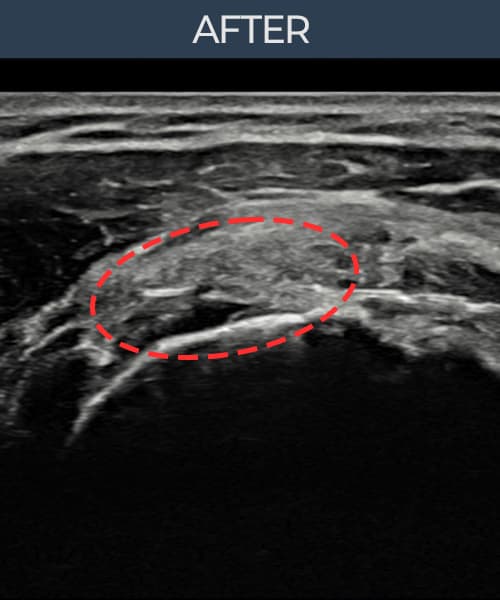

超声确认旋转肌腱袖 关节面侧部分撕裂(14mm × 7mm (肌腱厚度约68%缺损))。缩小缝合术后肌腱连续性恢复,患者回归正常生活。

术后

术前超声确认旋转肌腱袖 关节面侧部分撕裂,冈上肌腱回声不连续伴肌腱缺损(14mm × 7mm (肌腱厚度约68%缺损))。术后超声显示撕裂部位充满再生组织,肌腱连续性恢复,回声模式正常化。

该患者持续肩痛。详细超声检查确认旋转肌腱袖 关节面侧部分撕裂(缺损:14mm × 7mm (肌腱厚度约68%缺损))。在超声引导下实施非手术缩小缝合术。术后佩戴支具约4-6周,随后进行分阶段康复锻炼。随访超声确认肌腱连续性恢复、结构稳定,患者顺利回归日常生活。